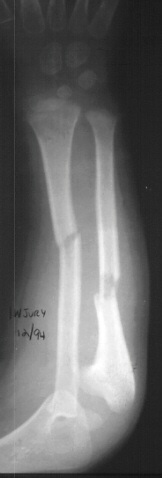

A 4 year and 6 month old male sustained a fall onto an outstretched left arm. He presented to the emergency room with forearm deformity and acute pain(image 1). It was treated with closed reduction and casting (image 2&3). The patient was brought back for another evaluation 10 months after the initial injury(image 4). An x-ray at that time was repeated. On physical examination, he has a prominence over the left radial head. There is full flexion and extension. He has full pronation but lacks 30 degrees of full supination. He is neurovascularly intact(image 5).